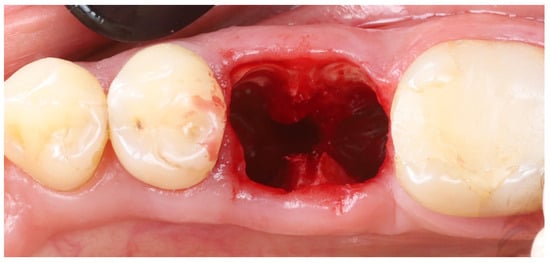

- Root sectioning: After performing mandibular nerve block anesthesia, the crown of tooth #36 (Figure 2A) was removed (decoronation was performed) (Figure 2B). The mesial and distal roots were then separated buccolingually using a long-shanked, straight diamond bur in a high-speed handpiece with copious irrigation (Figure 2C). The preoperative CBCT was consulted to guide the depth and orientation of the cuts, accounting for the roots’ length, curvature, and angulation.